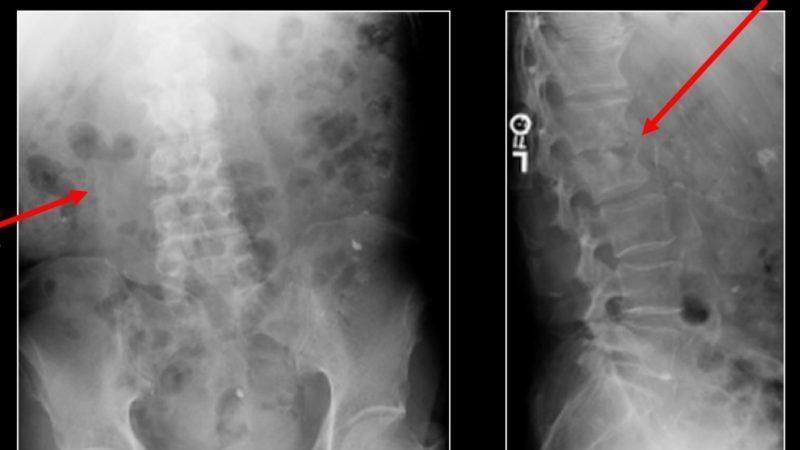

Диагностические мероприятия

Дополнительные исследования играют ключевую роль в диагностике воспалительных процессов в позвоночнике.

После детального осмотра врач рекомендует пациентам:

- Сдать анализы крови и мочи.

- Пройти рентгенографию в двух проекциях для выявления пораженной области.

- Сделать магнитно-резонансную томографию (МРТ).

- Пройти мультиспиральную компьютерную томографию (КТ).

Своевременная диагностика воспалительных заболеваний позвоночника и начало лечения имеют огромное значение. Специалист учтет причины заболевания, текущее состояние пациента и его индивидуальные особенности.